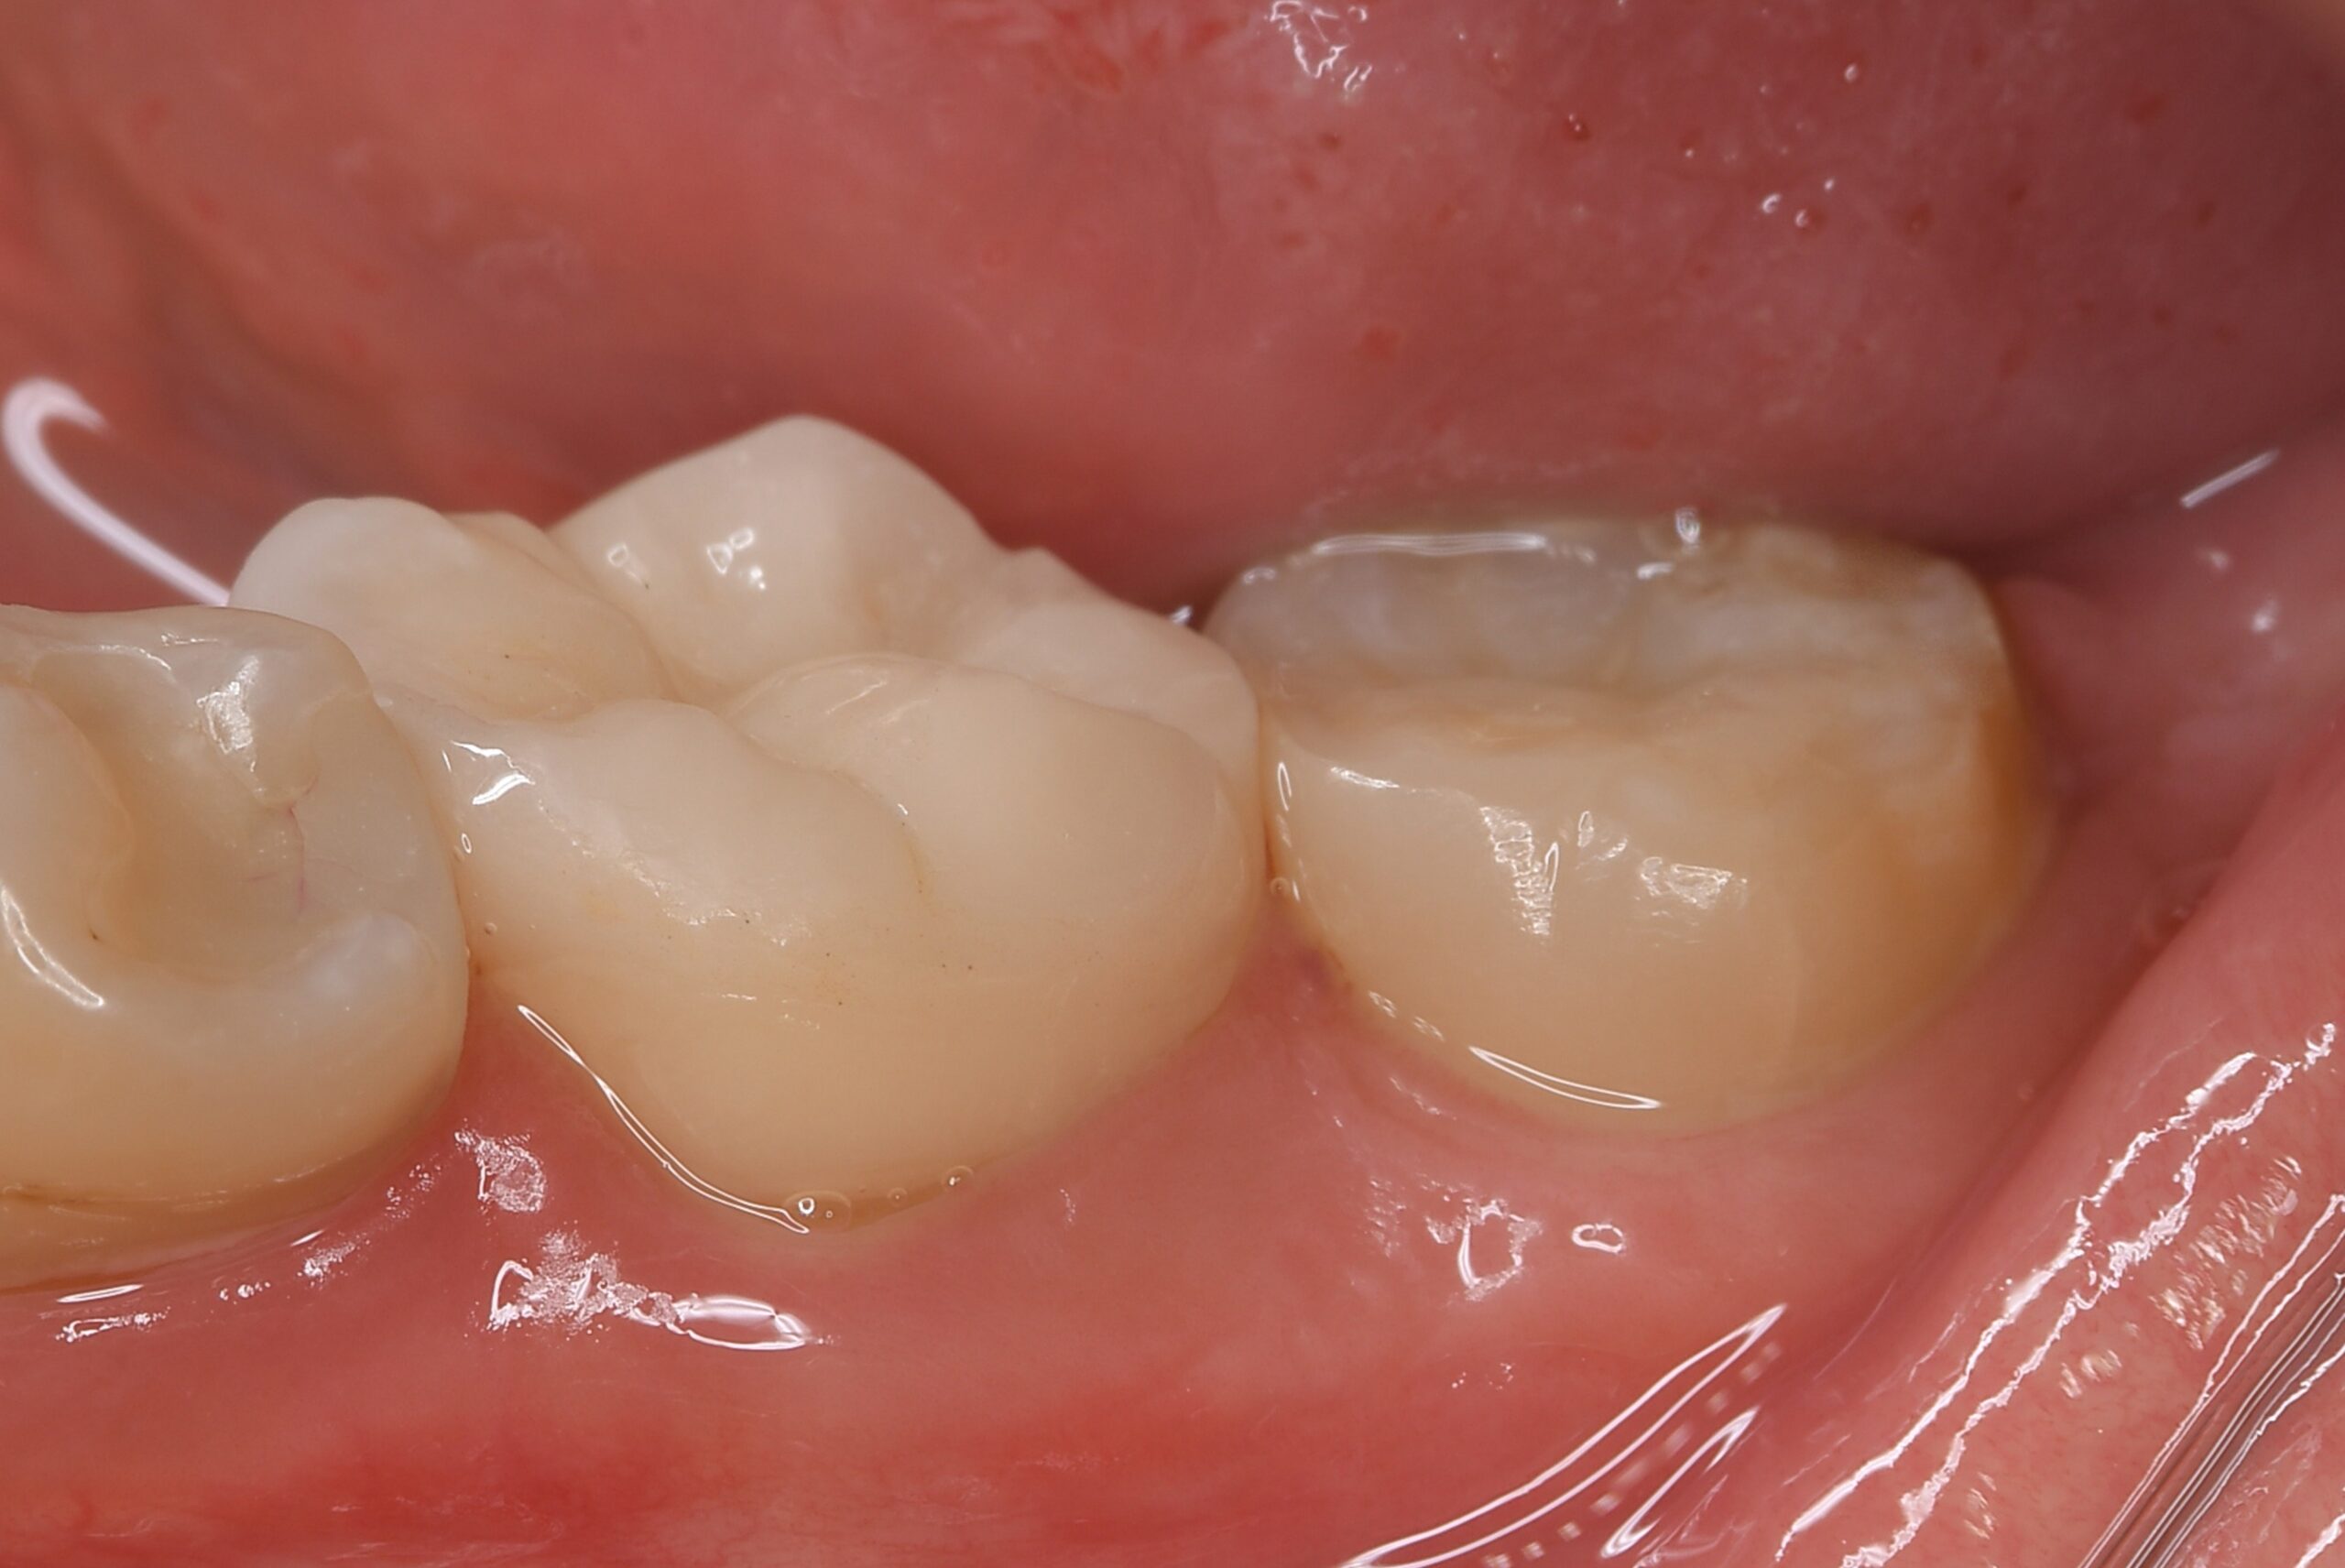

歯牙移植の症例

症例1

| 患者様データ | 30代 女性 |

| 来院時の主訴 | 「左下の歯グキが腫れてきた。」 |

| 医院の診断 | 慢性根尖性歯周炎、歯根破折 |

| 通院期間 | 8か月 |

| 来院回数 | 10回 |

| 治療費 | 総額:425,000円(税抜) 【内訳】 歯牙移植150,000円、精密根管治療80,000円(大臼歯)、ファイバーポストコア20,000円×2、セラミック治療85,000円、ダイレクトボンディング70,000円 |

| リスクと副作用 | ①根管治療歯は長期的には破折するリスク ②長期的なメインテナンスが必要 ③歯根の外部吸収 |

| ここがこだわりのポイント!☝ |

術前に撮影したCT画像から3Dプリンターを用いて親知らずのレプリカを作製することで、 親知らずが乾燥することを防ぎ、成功率が上がるよう努力しています。 |